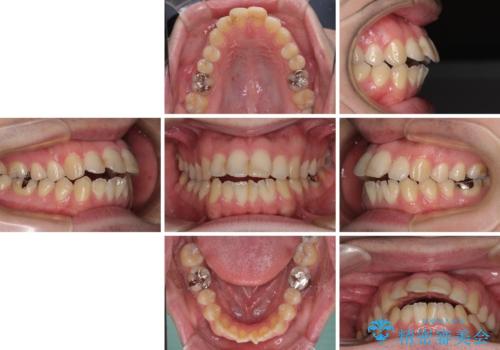

- 口がうまく閉じられないとのことで来院された患者様です。

上下唇をしっかり合わせようとすると、顎先が前方に突出してしまうほど口が閉じにくい状態でした。

口元の突出感を改善するために上下左右の第一小臼歯4本を抜歯し、ワイヤー装置にて矯正治療を行うこととしました。

また、上下前歯は舌の突出癖による開咬となっていたため、舌のトレーニングを徹底するよう指示しました。